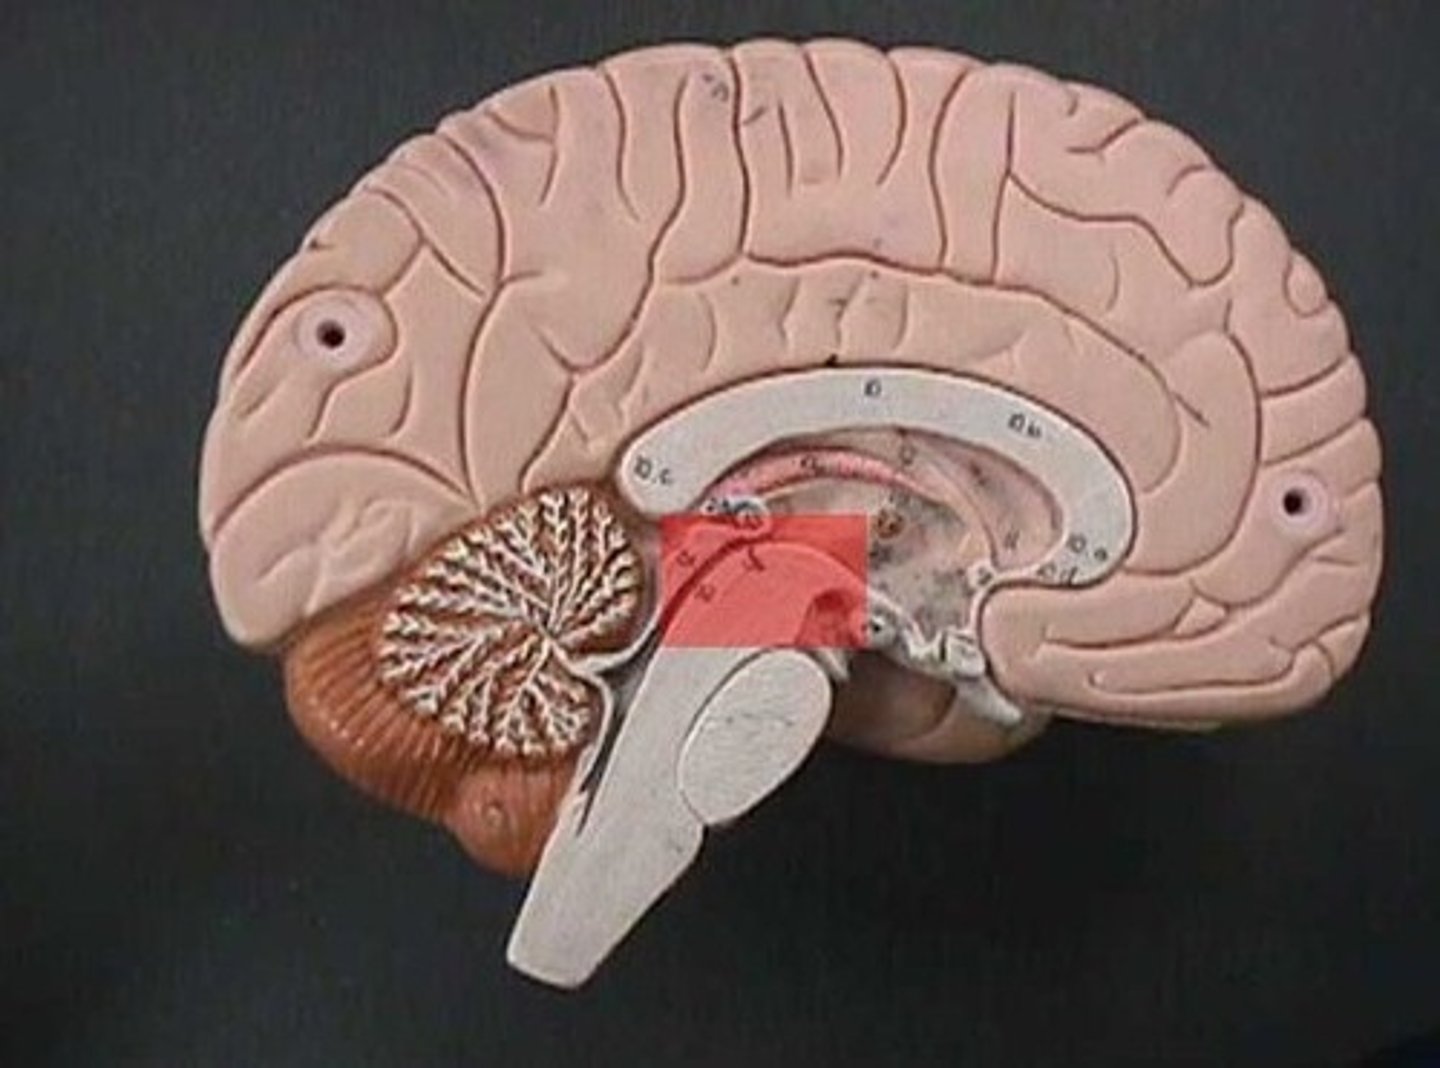

Identify structures of midsagittal brain

Corpus callosum

Diencephalon

thalamus, third ventricle, hypothalamus, epithalamus

Thalamus

Third Ventricle

Hypothalamus

Epithalamus (pink line)

Brain stem

Pons

Medulla oblongata

choroid plexus of third ventricle

produces cerebrospinal fluid

Third ventricle

cerebral aqueduct (midbrain)

midbrain

Fourth ventricle

Central Canal of brain

Takes Cerebrospinal fluid down to the spinal cord

Thalamus